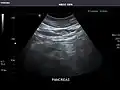

Left kidney -